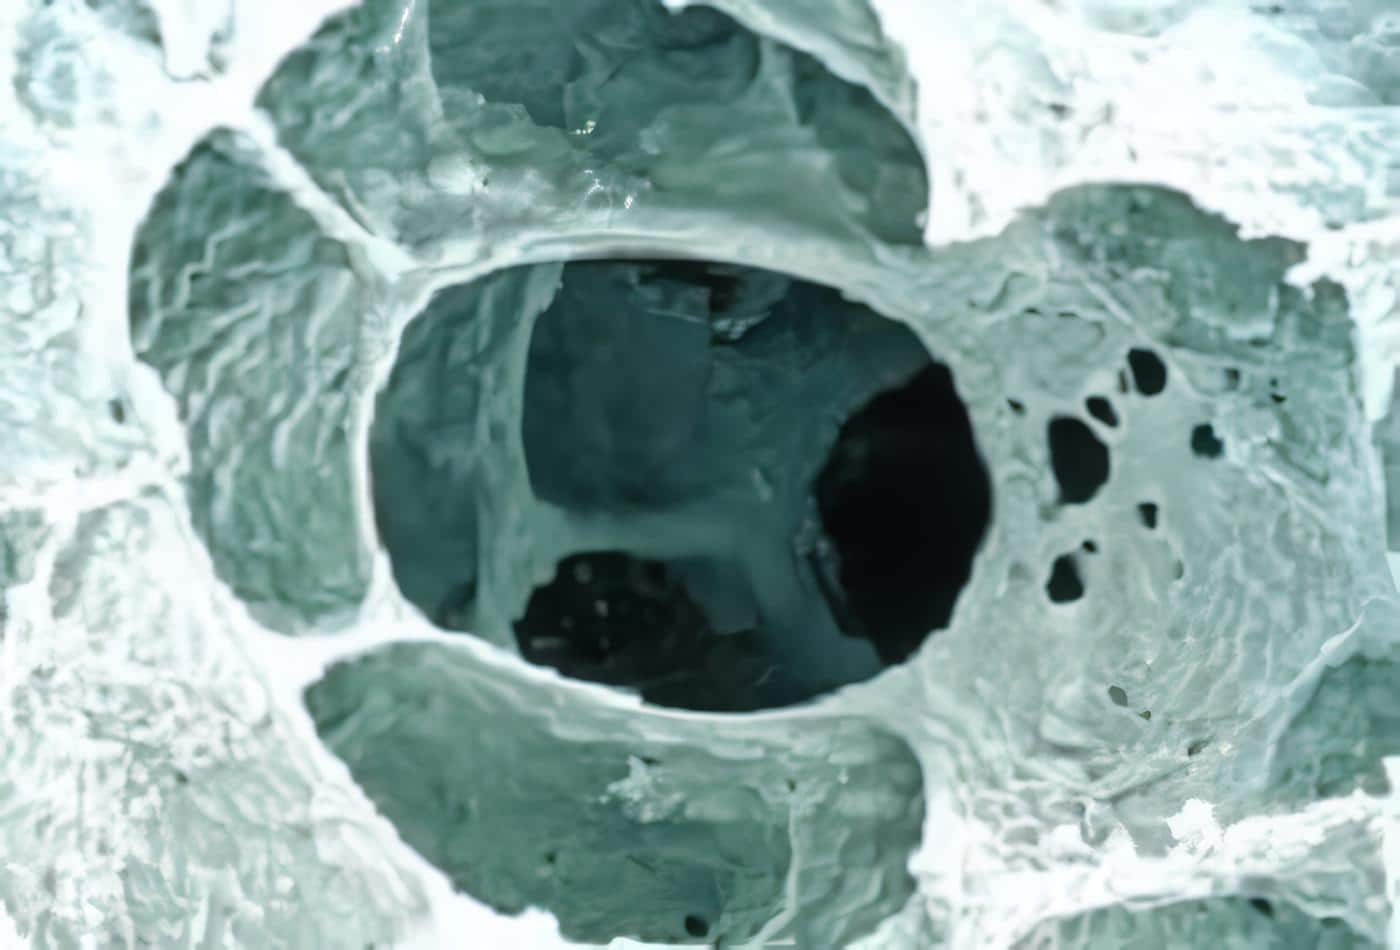

Colgajo muscular

El colgajo muscular se construye basado en el pedículo torácico largo para el serrato, o el toraco-dorsal para el dorsal ancho (ambos músculos se pueden rotar según la disponibilidad y necesidad), y se introduce a la cavidad torácica por una minitoracotomía accesoria en el segundo o tercer espacio intercostal, resecando una porción costal para permitir la entrada del músculo a la cavidad sin compresión del pedículo (Figura1).

El muñón bronquial y las fístulas parenquimatosas se cubren con el músculo (Figura 2). El tórax se deja abierto y empacado con compresas en ácido hipocloroso en una dilución 1/1000.